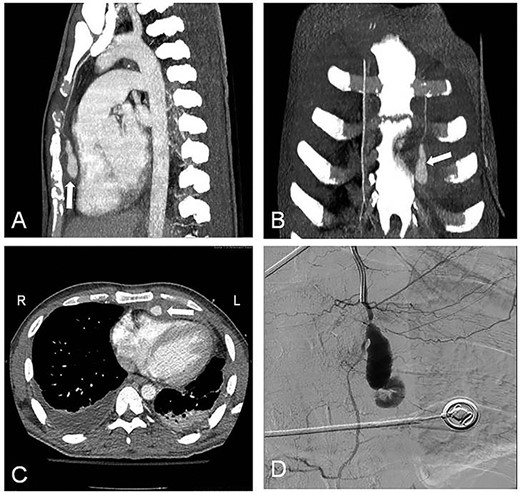

The embolization was performed after obtaining three consecutive negative blood cultures accompanied by a significant decrease of the laboratory infection parameters. The angiographic approach was done through the left brachial artery (Fig. 1D), and a microcatheter was placed into the aneurysm neck. Through coiling we aimed to occlude the IMA distally and proximally adjacent to the aneurysmatic sac, but attempts to cannulate the vessel distal to the aneurysm were unsuccessful. Therefore multiple (5x) coils were placed (VortX™ 35 (3×) and Complex Helical 18 (2×); Boston Scientific; Boston, MA, USA) into the aneurysmatic neck and sac (Fig. 2A).

(A) Coil embolization of the aneurysm; (B) postembolization completion angiogram; (C) follow-up contrast-enhanced CT scan at 3 weeks after the embolization with complete regression of the pseudoaneurysm without flow into it (white arrow); (D) follow-up contrast-enhanced CT scan at 6 months after the embolization.

The completion angiogram demonstrated no filling in the coiled pseudoaneurysmal sac (Fig. 2B), while at follow-up 1, 3 weeks and 6 months after the procedure, CT scans showed initially shrinkage and finally complete regression of the pseudoaneurysm with no flow into it (Fig. 2C and D; white arrow). Early post-interventional course was unremarkable, and the patient was discharged after completing an intravenous antibiotic treatment over 6 weeks.